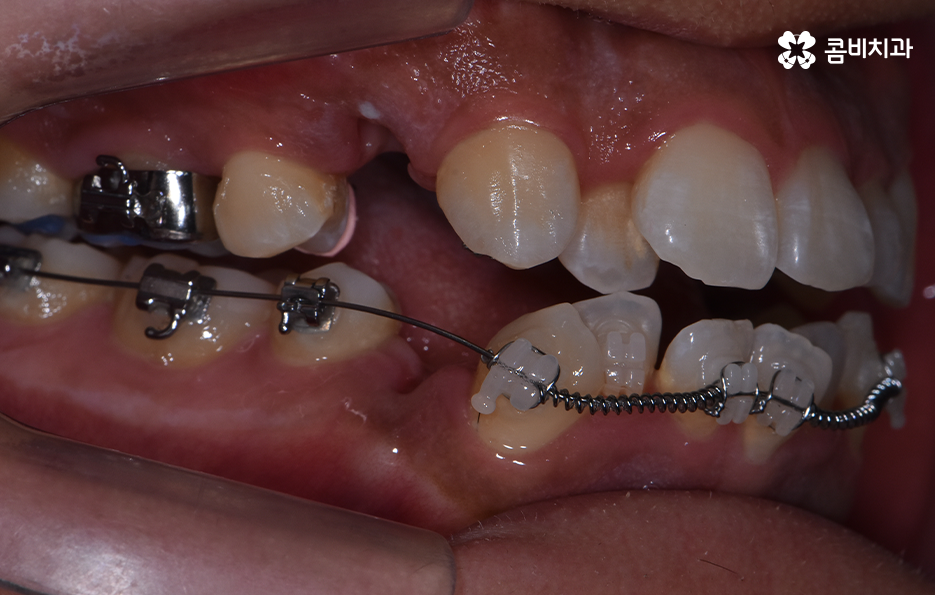

치아교정을 위한 발치교정 과정은 대부분 소구치 라고 불리는 첫번째 작은 어금니를 발치하게 되며 좌우, 위 아래 총 4개의 소구치를 발치한 후에 덧니가 재배열 될 수 있는 공간을 만들기 위하여 우선 송곳니를 후방으로 이동시키고 있어요

그 다음으로는 송곳니가 후방으로 이동하면서 확보된 공간으로 앞니의 배열을 가지런하게 맞추고 있는데요. 앞니의 재배열과 함께 발치 교정으로 인해 빈 공간이 발생한 부분을 없애고 전체적인 치열을 미세하게 조절하게 되는데 발치교정은 치아의 움직임이 많은 편이기 때문에 교합이 잘 맞도록 마무리 배열을 잘해야 하며 그와 함께 치아가 많이 움직이는 만큼 얼굴형의 변화와 입술라인 등의 변화가 클 수 있다는 점에서 치료 후 결과를 잘 예측하여 처음 치료 계획부터 마무리까지 섬세하게 진행하실 필요가 있어요